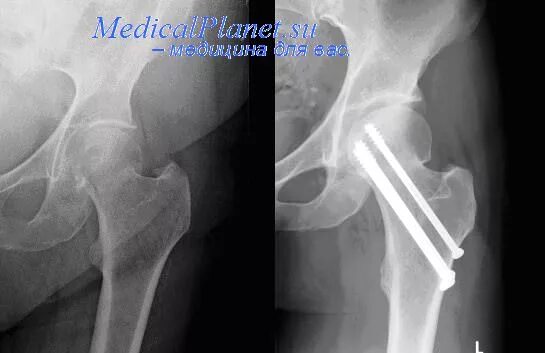

Нестабильность тазобедренного сустава